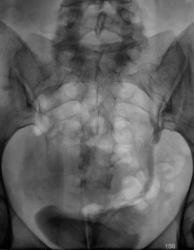

Почки контурируются в типичном месте, обычной формы и размеры. R-позитивных уроконкрементов в проекции мочевыносящих путей на обзорной урограмме не выявлено. ЧЛС контрастированы синхронно, не расширены. Мочеточники контрастированы, левый просматривается на всем протяжении, в нижней 1/3 незначительно стойко расширен, оттеснен кверху и вправо (хотя возможен такой вариант расположения устьев мочеточников - к сожалению правый мочеточник не визуализируется т.е. несчем сравнить). В мочевом пузыре, слева от срединной линии, дефект наполнения с четкой неровной границей.

Валентин Львович! Дефект наполнения мочевого пузыря слева имеется. Сказать вне пузырный или внутрипузырный сложно. Я бы выполнил УЗИ мочевого пузыря. Урологам порекомендовал бы цистоскопию.

Согласен с последним постом; думаю после УЗИ мочевого пузыря вопросов будет меньше( вообще, в данной клинической ситуации оптимальнее было бы начать с УЗИ мочевыводящей системы).

Валентин Львович томограмки у вас хорошие получились, а как вы это расценили? Лично мне кажется это от давления из вне, а по поводу УЗИ, разве оно не входит в алгоритм обследования пациентов с МКБ и почечной коликой у вас в больнице?